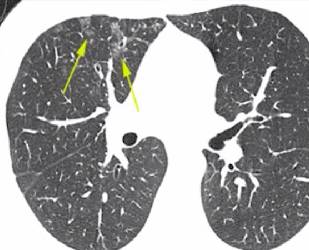

科学指引,助力肺纤维化患者冲破误诊与绝望迷雾|与光同行浙江大学医学院附属邵逸夫医院呼吸与危重症医学科副主任医师 邱婷当在CT检查报告上看见“特发性肺纤维化”这七个字时,63岁的货车司机... 她向张敏一家耐心地解释:“如果疾病是一辆车的话,CT可以展示车的外观和内饰,能让我们看到肺的大致情况。但这辆车在高速上能跑多快、动...